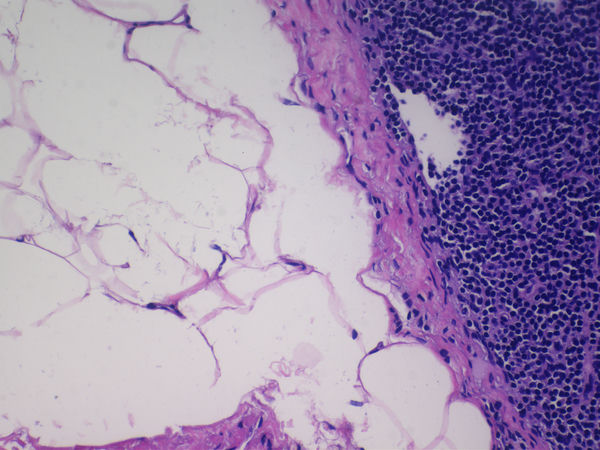

通过将生物组织处理成薄片并放置于玻片上,利用生物显微镜和显微镜相机,可以观察并记录下切片组织结构和细胞的微观特征。显微数字镜相机MSX11搭配奥林巴斯生物显微镜CX33,样品图像准确还原切片组织的精细结构和真实色彩。

显微镜数字相机MSX11采用高性能成像芯片,内置MS系列硬件ISP图像处理芯片,针对显微镜拍摄场景特别优化,精准还原样品的精细结构和真实色彩,通过硬件加速,大大提升了相机运行速度,是荧光拍摄、病理诊断、金相分析和体视观察等应用领域的理想工具。